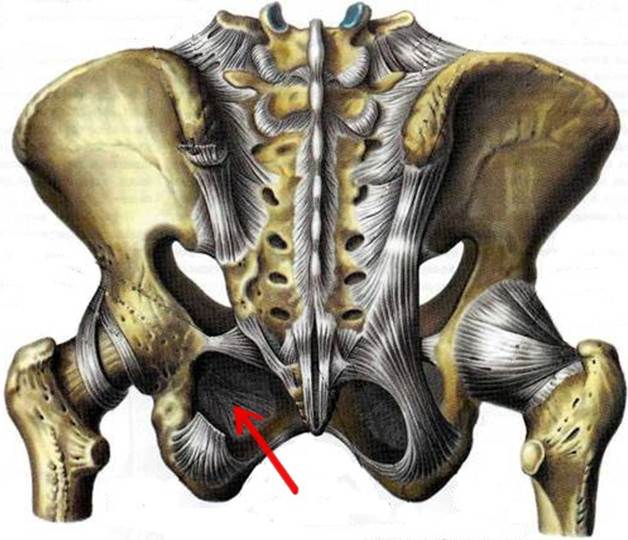

S: Стрелка указывает на zona orbicularis

S: Стрелка указывает на lig. Ischiofemorale

S: Стрелки указывают на lig. iliofemorale

S: Стрелка указывает на lig. pubofemorale